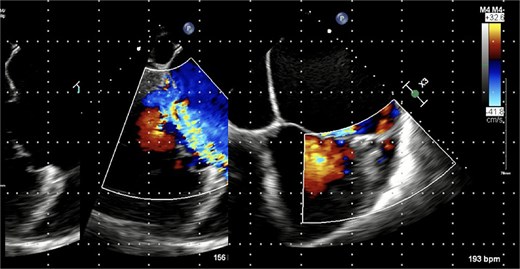

Chest radiograph demonstrated pulmonary oedema (Fig. 1) and transoesophageal echocardiography (TOE) demonstrated a flail P2 segment with an anteriorly directed jet of severe MR, vena contracta 8 mm, effective regurgitant orifice area 0.55 cm2 (Fig. 2). Left ventricle was severely dilated (LVEDD 72 mm) with ejection fraction 35%. Both atria and the left ventricle were dilated. No vegetations were seen. He was cardioverted to sinus rhythm with 200 J biphasic shock.